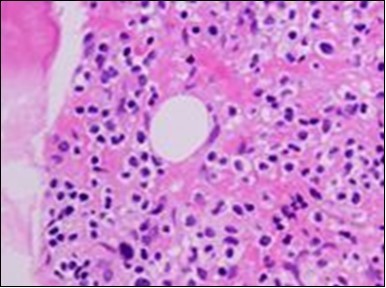

Figure 2.HCL: hairy cells with projecting cytoplasm abutting bony trabaculae(18).

HCL: hairy cells with                        projecting cytoplasm abutting bony trabaculae(18).